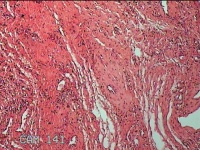

右侧外阴囊肿囊壁

性别

女

年龄

35岁

临床诊断

右侧前庭大腺囊肿

一般病史

发现右侧外阴囊肿1年。

标本名称

大体所见

白暗红色囊性肿物2.3x1.5x0.8cm一个,表面光滑,部分已切开,囊内容物已流失,囊壁厚0.1cm。

良性病变。